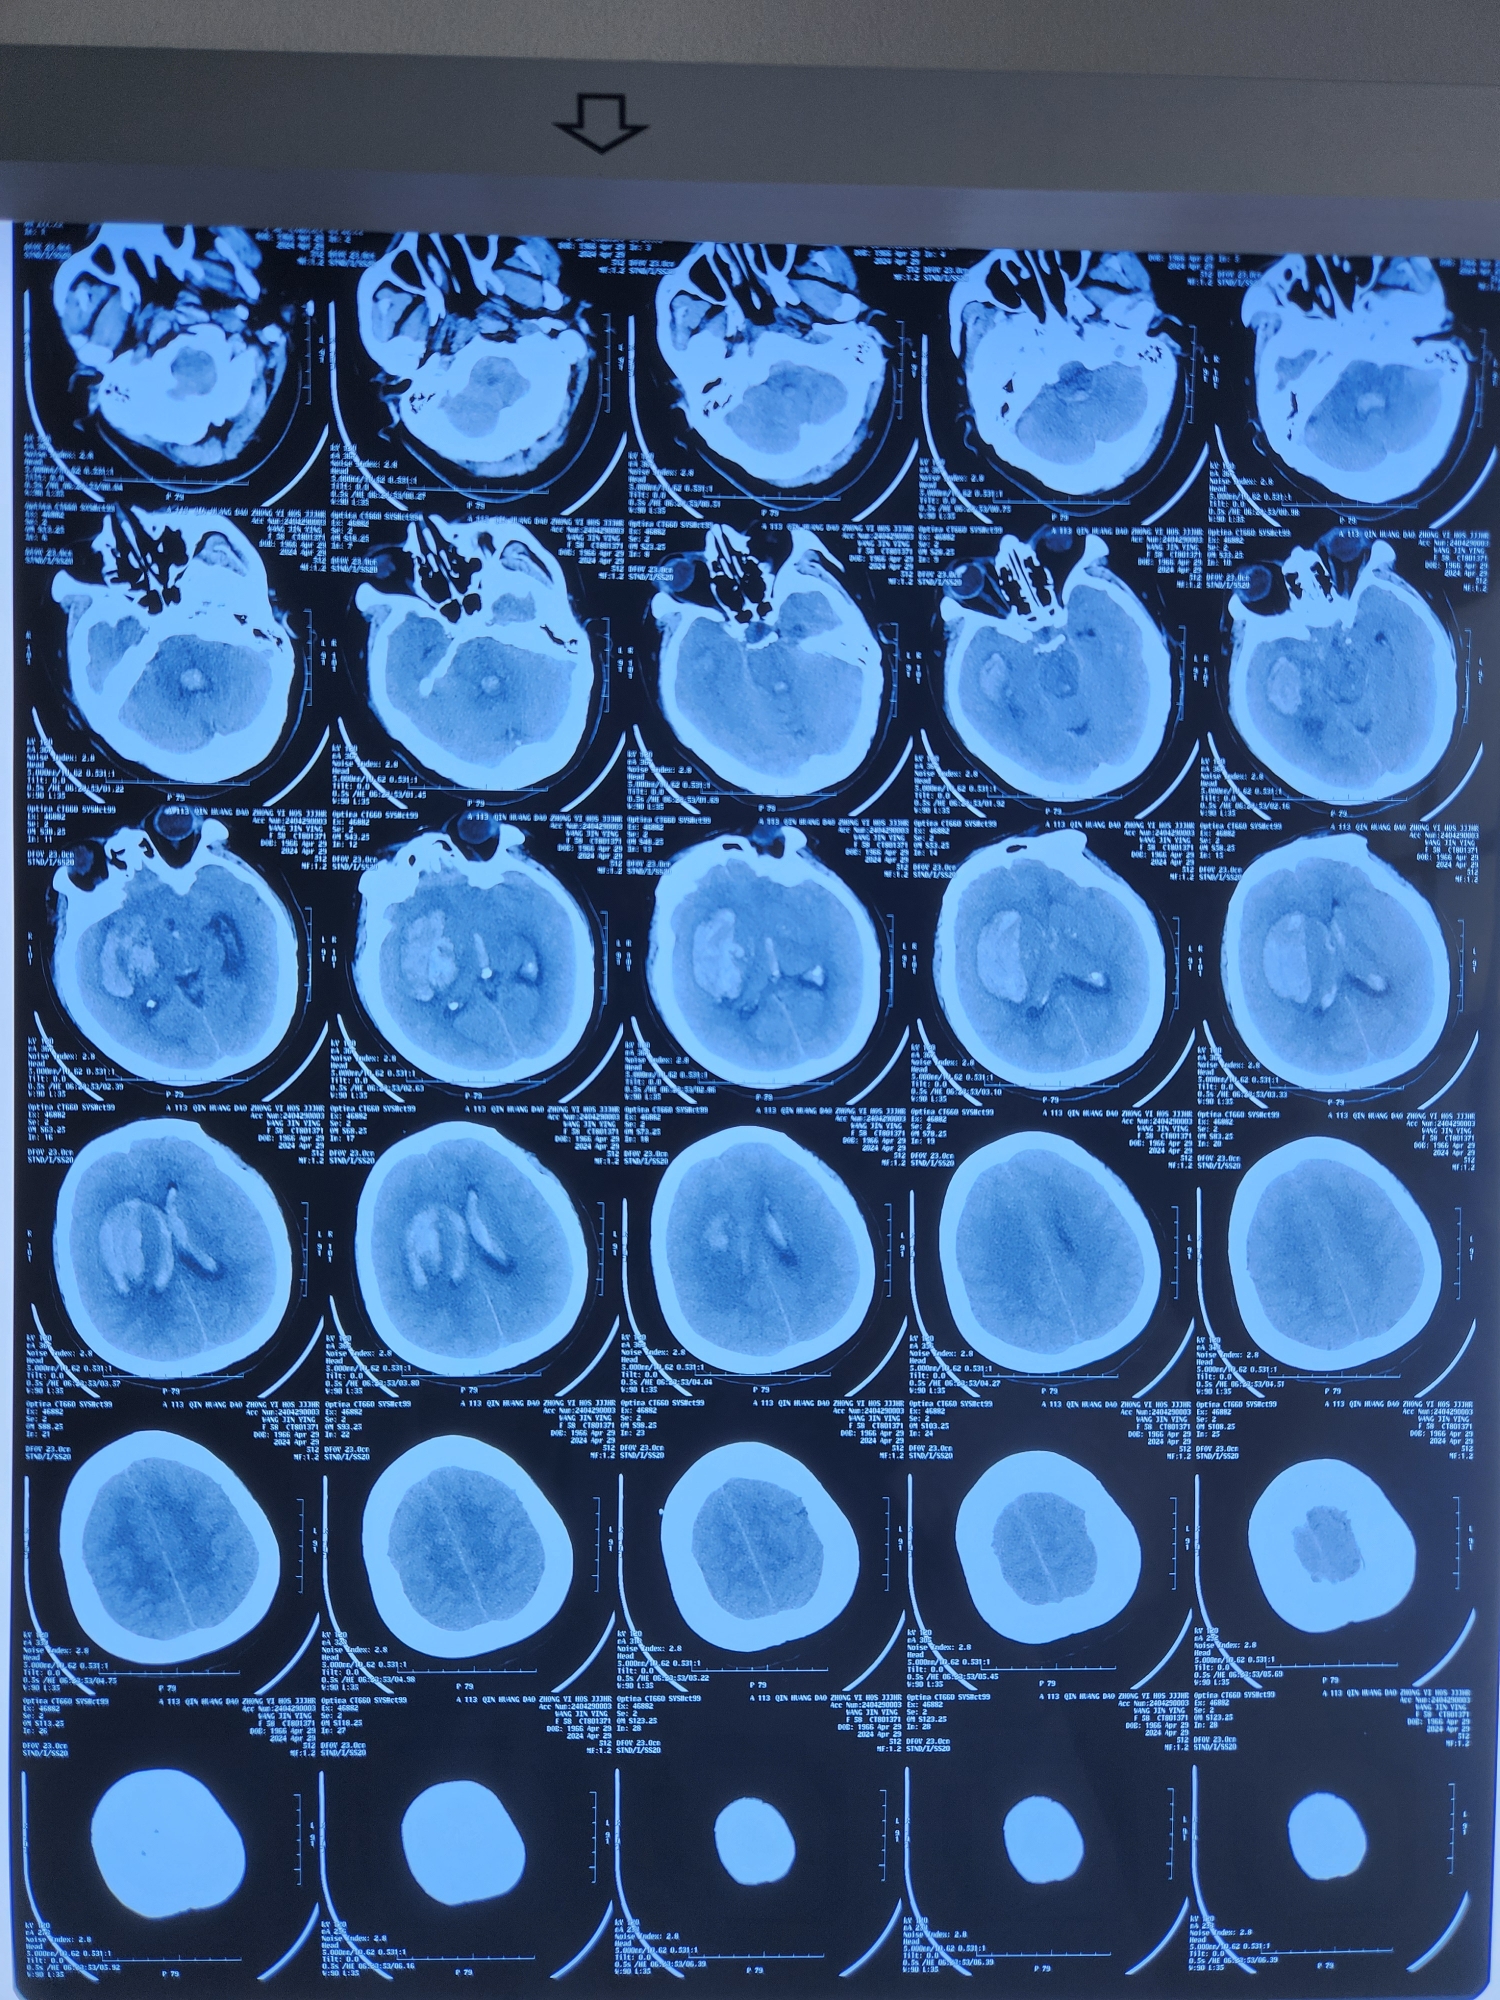

患者为中年女性,突发意识不清入院,外院CT提示右侧基底节出血破入脑室。

术前CT

术后CT